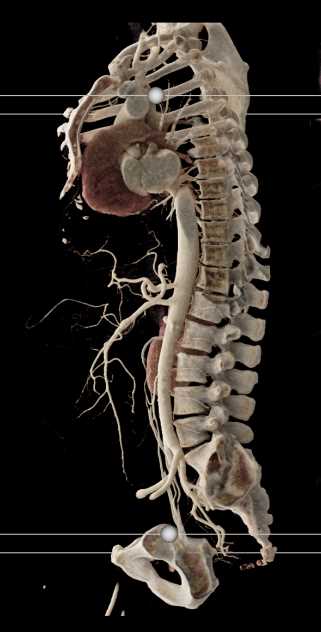

SMA Stenosis